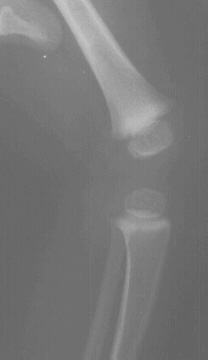

This 29 week gestation male was born by vaginal delivery. These x-rays were made after it was noted that that the knees appeared to be hyper-extended. The right knee had -30 degrees extension to 20 degrees of flexion. The left knee had -20 degrees extension to 20 degrees of flexion. Ortolani exam revealed a positive sign in the left hip and a negative sign in the right. Knee splints were applied. In two weeks the knees were able to flex to 75 degrees bilaterally.

A grade three knee dislocation means the tibial plateau has no contact with the femoral condyles and this usually requires an open reduction with the knee being fixed with crossed K- wires.